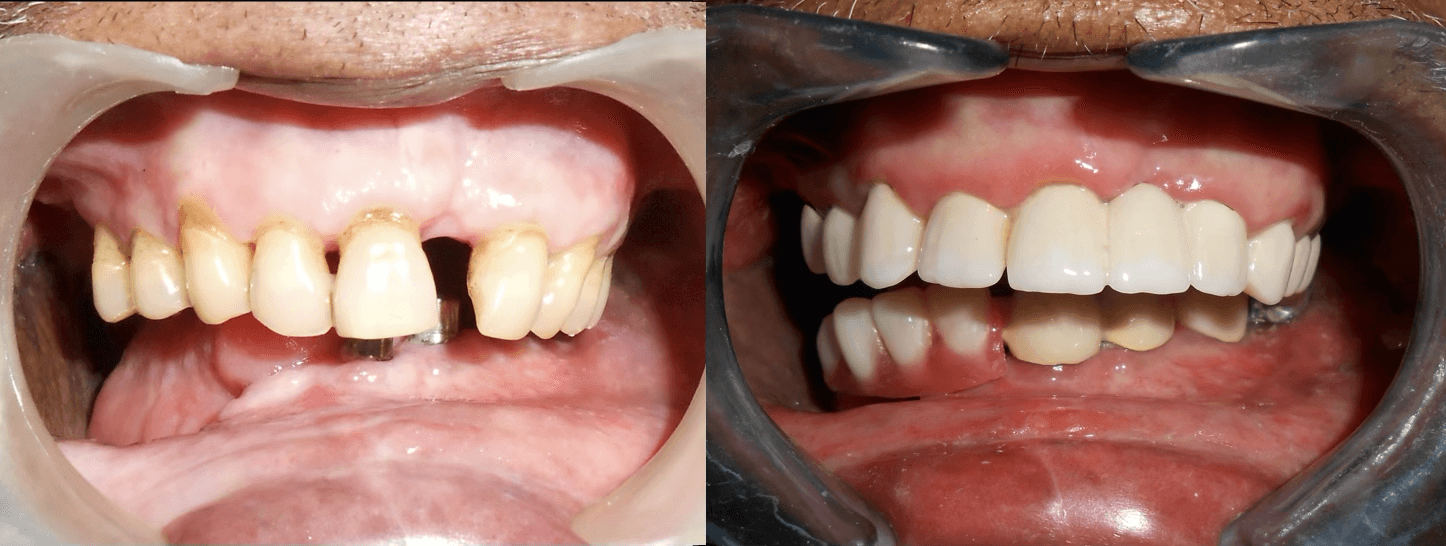

Initial condition

Final result

A 72-year-old male oral cancer survivor visited our dental center after surgical removal of the right side of his mandible. Patient had multiple missing and attrited teeth with significant functional impairment. Treatment involved implant-supported lower teeth with PFM crowns and precision-attached removable denture for hemimandibulectomy rehabilitation.

PFM crowns were fabricated and fixed for the upper remaining teeth to restore function and aesthetics.